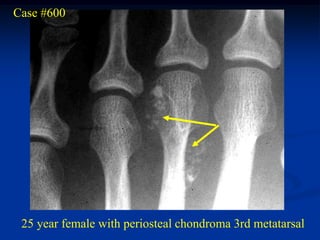

Case #600

25 year female with periosteal chondroma 3rd metatarsal